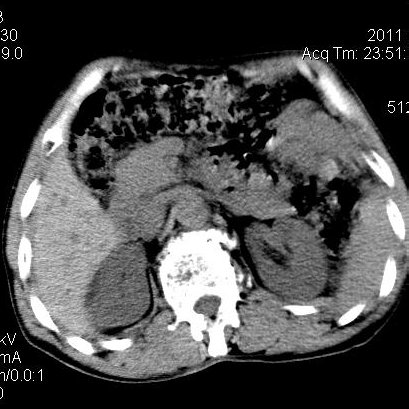

肝左叶发育异常

男性,55岁,骑摩托车摔倒后入院,自述右上腹疼痛

[backcolor=#FF0000]第一次诊断的时候也是这么肯定,可是床旁超声检查并没有发现明显异常,而且患者的一般症状都良好。还好临床只是保守治疗,没有立即手术,第二次复查的时候没有一点变化,又做了MRI检查,没有血肿,

这是一例肝左叶发育异常的,很个性吧~[/backcolor]